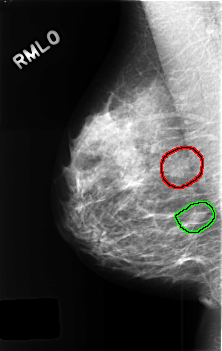

C_0437_1.RIGHT_MLO

RIGHT_MLO LINES 4560 PIXELS_PER_LINE 2880 BITS_PER_PIXEL 12 RESOLUTION 50 OVERLAY

FILE: C_0437_1.RIGHT_MLO.OVERLAY

TOTAL_ABNORMALITIES 2

ABNORMALITY 1

LESION_TYPE MASS SHAPE FOCAL_ASYMMETRIC_DENSITY MARGINS N/A

ASSESSMENT 3

SUBTLETY 3

PATHOLOGY BENIGN_WITHOUT_CALLBACK

TOTAL_OUTLINES 1

ABNORMALITY 2